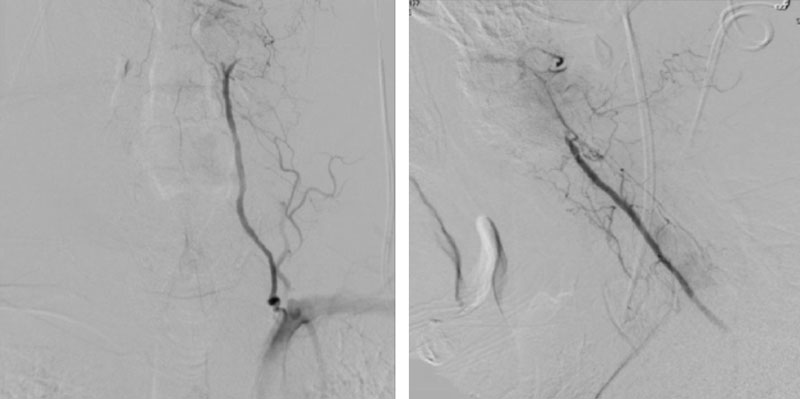

CTA of the neck and brain reveal that the left Vertebral Artery is completely occluded at approximately the C1-C2 level with extensive hypertrophic degenerative osseous changes from C1-C3. Retrograde flow into the post PICA left Vertebral Artery is observed from the co-dominant right Vertebral Artery which appears to be the primary supply into the basilar circulation. No significant Posterior Communicating arteries are observed on either the right or left Carotid Artery on the CTA imaging (Figure 1).

We performed conventional catheter angiography with provocative testing to reproduce his symptoms. The right Vertebral Artery is the codominant primary supply to the basilar circulation with reflux into the distal left Vertebral Artery that is occluded (Figure 3).

During neutral positioning, the vertebrobasilar circulation fills briskly from the Right Vertebral Artery. (Figure 4)

On rotation to the left, the patient experienced mild symptoms, however no significant Vertebral Artery or basilar reduction in flow was observed. On rotation to the right, the patient experiences slightly more moderate symptoms, however no significant Vertebral Artery or vascular reduction flow was observed. On hyper extension of approximately 10-15 degrees, passively performed by the patient until symptoms are reproduced, angiogram demonstrates complete occlusion of the right Vertebral Artery at approximately the C2-C1 level. (Figure 5)